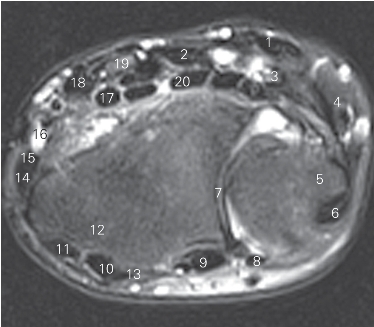

图4-38 经远侧尺桡关节的横断层MR T2WI FS

1 尺侧腕屈肌 flexor carpi ulnaris

2 指浅屈肌 flexor digitorum superficialis

3 尺神经 ulnar nerve 4 小鱼际 hypothenar

5 尺骨 ulna 6 尺侧腕伸肌 extensor carpi ulnaris

7 远侧尺桡关节 distal radioulnar joint 8 小指伸肌 extensor digiti minimi

9 指伸肌 extensor digitorum

10 桡侧腕短伸肌 extensor carpi radialis brevis

11 桡侧腕长伸肌 extensor carpi radialis longus

12 桡骨 radius 13 拇长伸肌 extensor pollicis longus

14 拇短伸肌 extensor pollicis brevis

15 拇长展肌 abductor pollicis longus

16 桡动脉 radial artery

17 拇长屈肌 flexor pouicis longus 18 桡侧腕屈肌 flexor carpi radialis

19 正中神经 median nerve

20 指深屈肌 flexor digitorum profundus